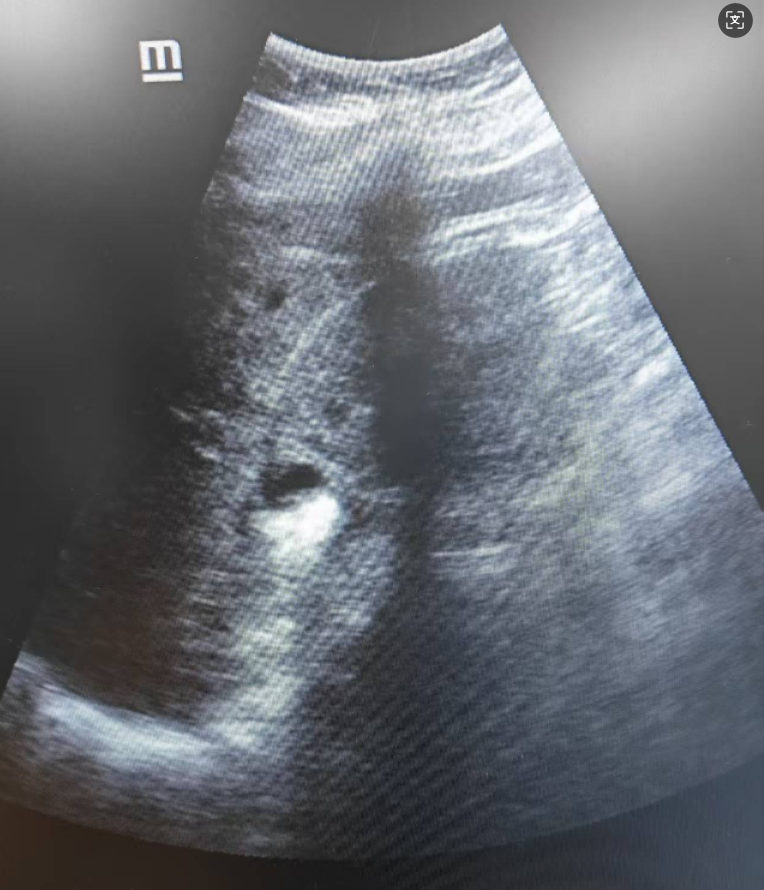

面对这一特殊情况,我院专家团队迅速调整思路,结合术前CT与术中实时超声定位,判断患者可能存在较为特殊的“肾盏憩室结石”。专家团队果断寻及闭合的盏颈口,借助钬激光技术切开后,结石终于显露。主刀医师随后将结石击碎并悉数取出,同时解除了盏颈梗阻,成功完成了手术。

▲B超实时定位